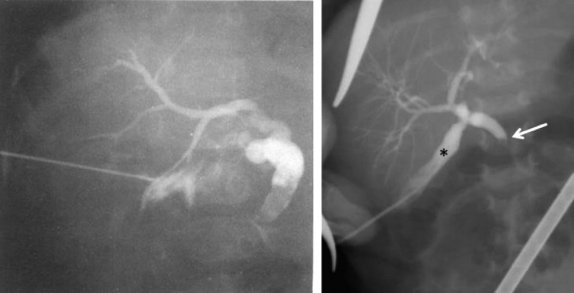

Для диагностики синдрома сгущения желчи используется также и интраоперативная холангиография через пунктированный желчный пузырь, позволяющая выявить полную обструкцию общего желчного протока с дилатацией пузырного протока и печеночного протока (рис. 4).

Рисунок 4. Синдром сгущения желчи. Чрескожная холецистохолангиография через пунктированный желчный пузырь. Дилатация и обрыв общего желчного протока и умеренная дилатация интрапеченочных желчных протоков [24, 25]

Figure 4. Bile thickening syndrome. Percutaneous cholecystocholangiography via a gallbladder puncture. Dilatation and rupture of the common bile duct and moderate dilatation of the intrahepatic bile ducts [24, 25]

Терапия синдрома сгущения желчи у детей раннего возраста включает хирургические и консервативные методы. В оперативном лечении, позволяющем восстановить пассаж желчи в двенадцатиперстную кишку, нуждаются менее 4% детей с синдромом сгущения желчи (рис. 4). Исторически первым хирургическим вмешательством была лапаротомия с последующей ирригацией через доступ в общий желчный проток или желчный пузырь, выполненная W.E. Ladd в 1935 г. [7, 26].